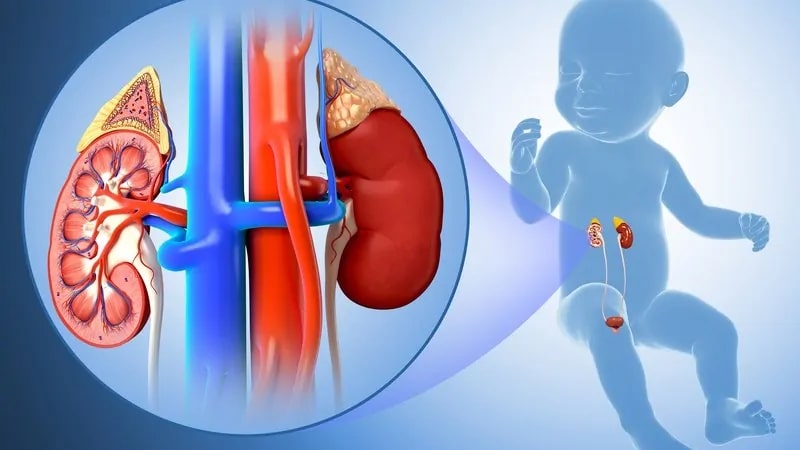

Hội chứng thận hư ở trẻ em

Hội chứng thận hư vô căn là thể bệnh thận hư thường gặp nhất ở trẻ em, chiếm hơn 90% các trường hợp ở trẻ từ 1-10 tuổi, trong đó sang thương cầu thận tối thiểu chiếm đến 75%.